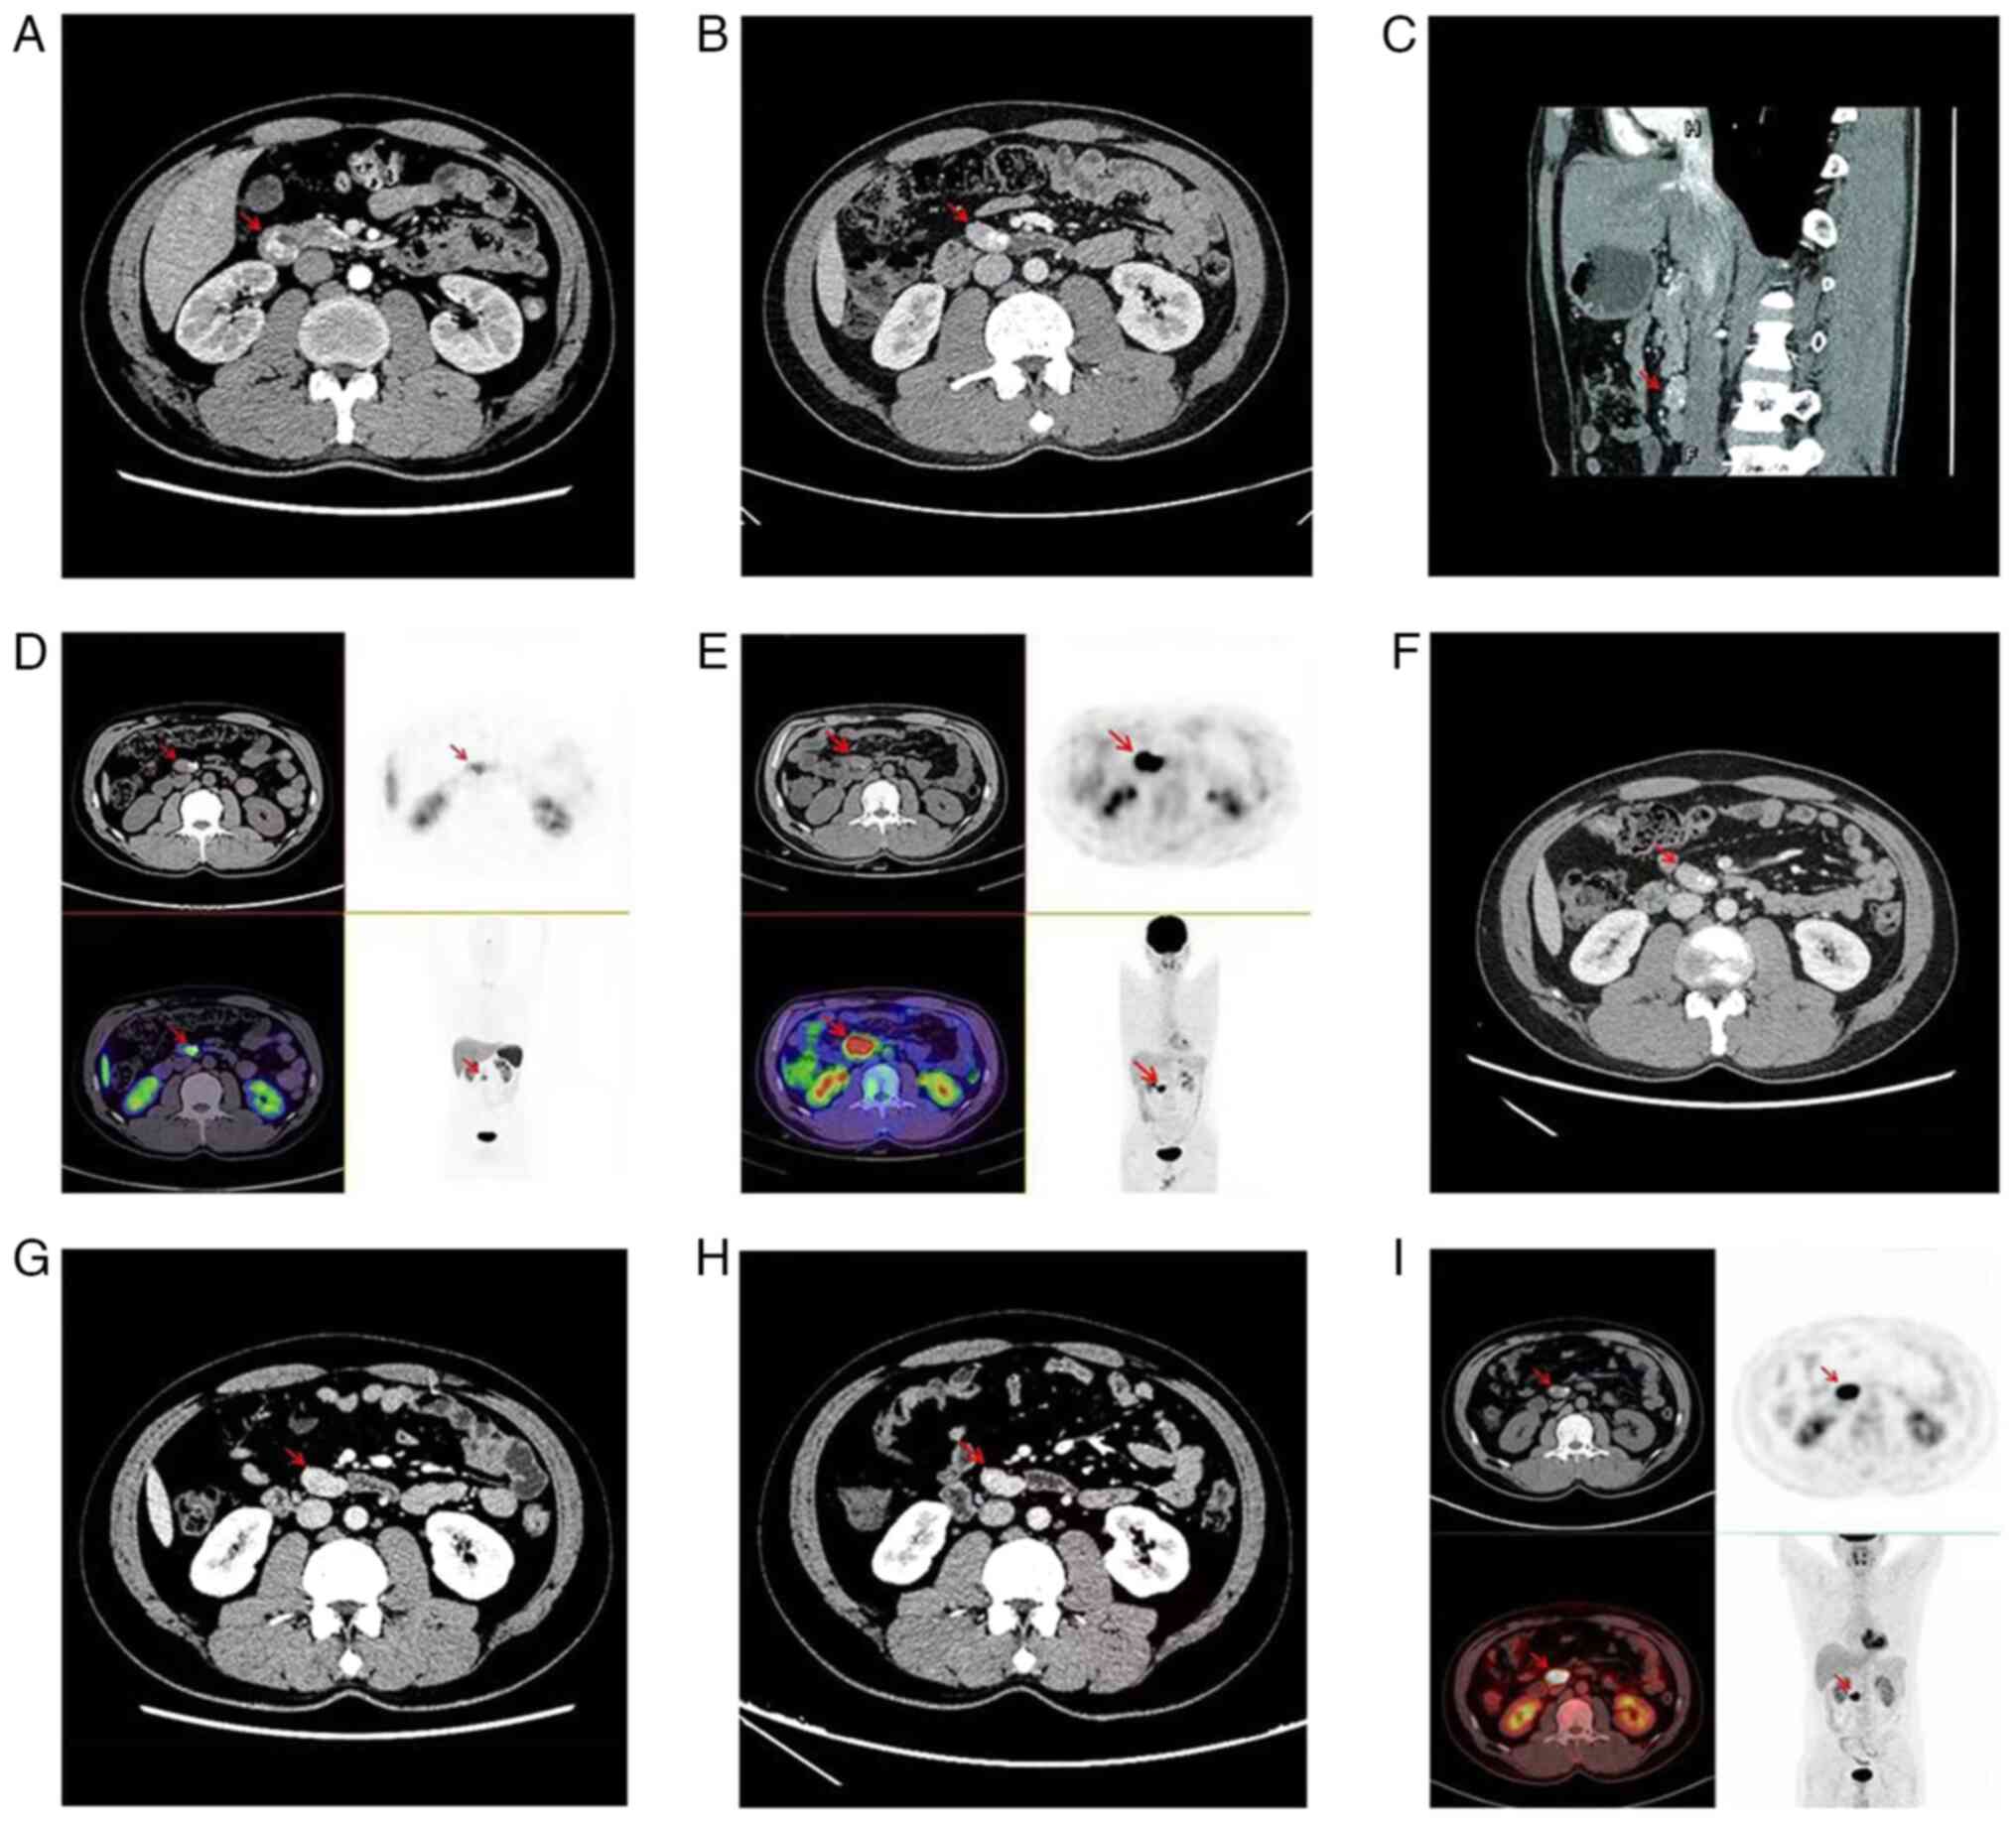

Treatment and management of duodenal gangliocytic paraganglioma: A case report

Gangliocytic paraganglioma (GP) is a rare neuroendocrine tumor primarily found in the duodenum, most commonly in the second and third sections of the duodenum. Diagnosis of GP is based on its distinctive histopathological characteristics, which include three types of tumor cells in varying proportions: i) Epithelioid, ii) spindle‑like and iii) ganglion‑shaped cells. The distribution of the three tumor cell components varies from case to case and a patient may be easily misdiagnosed if one of the components is predominant. Endoscopic submucosal dissection (ESD) or surgical resection is the ideal treatment for duodenal GP (DGP); however, biotherapy, nuclide therapy, chemotherapy, targeted therapy and immunotherapy can be selected individually for patients with postoperative recurrence, metastasis or not suitable for surgery. In the present study, a male patient with DGP experienced recurrence after ESD surgery, and so received octreotide (Novartis; 30 mg/28 days) for 12 consecutive cycles. The patient had no further symptoms of gastrointestinal bleeding and no new lesions or metastases were observed after 47 months of follow‑up.

Figure 1